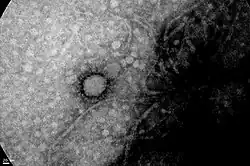

Virus strain | SARS-CoV-2 |

The COVID-19 pandemic in Argentina is part of the worldwide pandemic of coronavirus disease 2019 (COVID-19) caused by severe acute respiratory syndrome coronavirus 2 (SARS-CoV-2). As of 21 August 2025, a total of 10,113,909 people were confirmed to have been infected, and 130,783 people were known to have died because of the virus.[3]